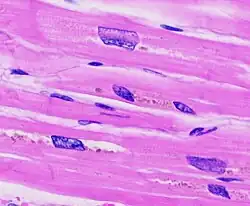

Ventricular hypertrophy (VH) is thickening of the walls of a ventricle (lower chamber) of the heart.[1] Although left ventricular hypertrophy (LVH) is more common, right ventricular hypertrophy (RVH), as well as concurrent hypertrophy of both ventricles can also occur.

The ventricles are the chambers in the heart responsible for pumping blood either to the lungs (right ventricle) or to the rest of the body (left ventricle). Ventricular hypertrophy may be divided into two categories: concentric hypertrophy and eccentric hypertrophy. These adaptations are related to how the cardiomyocyte contractile units, called sarcomeres, respond to stressors such as exercise or pathology. Concentric hypertrophy is a result of pressure overload on the heart, resulting in parallel sarcomerogenesis (addition of sarcomere units parallel to existing units). Eccentric hypertrophy is related to volume overload and leads to the addition of sarcomeres in series.[3]

Concentric hypertrophy is characterized by an addition of sarcomeres (the contractile units of cardiac cells) in parallel. The result is an increase in thickness of the myocardium without a corresponding increase in ventricular size. This is maladaptive largely because there is not a corresponding proliferation of the vasculature supplying the myocardium, resulting in ischemic areas of the heart. Ultimately, this response can be compensatory for a duration, and allow for improved cardiac function in the face of stressors. However, this type of hypertrophy can result in a dilated ventricle which is unable to effectively pump blood, leading to heart failure.[5] When stressors that encourage this concentric hypertrophy are reduced or eliminated (either surgically corrected in the case of cardiac defects, or hypertension is reduced from diet and exercise) it is possible for the heart to undergo 'reverse remodeling', returning to a somewhat more 'normal' state instead of progressing to a dilated, pathologic phenotype. This reversion may even go beyond muscle mass, and repair abnormalities in cardiac connective tissue.[4]

Eccentric hypertrophy is generally regarded as healthy, or physiologic hypertrophy and is often termed "athlete's heart." It is the normal response to healthy exercise or pregnancy,[6] which results in an increase in the heart's muscle mass and pumping ability. It is a response to 'volume-overload', either as a result of increased blood return to the heart during exercise, or a response to an actual increase in absolute blood volume as in pregnancy. This increase in pumping ability is the result of the addition of sarcomeres in series, which enables the heart to contract with greater force.[7] This is explained by the Frank Starling mechanism, which describes the sarcomere's ability to contract with greater force as more of the elements of its contractile units become engaged. This response can be dramatic; in trained athletes have hearts that have left ventricular mass up to 60% greater than untrained subjects. Rowers, cyclists, and cross-country skiers tend to have the largest hearts, with an average left ventricular wall thickness of 1.3 centimeters, compared to 1.1 centimeters in average adults. Though eccentric hypertrophy is termed 'athlete's heart' it is typically only found in individuals who are aerobically conditioned. For example, weight lifters tend to undergo remodeling which more closely resembles concentric hypertrophy, as the heart does not experience a volume-overload, but instead responds to transient pressure overload as a consequence of increased vascular resistance from pressures exerted on arteries by sustained muscular contraction.